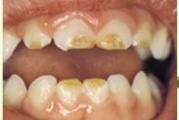

Tetratsükliini liigtarbimise tõttu värvunud hambad

Fluoroos

Fluoroosi

Emaili hüpoplaasiad